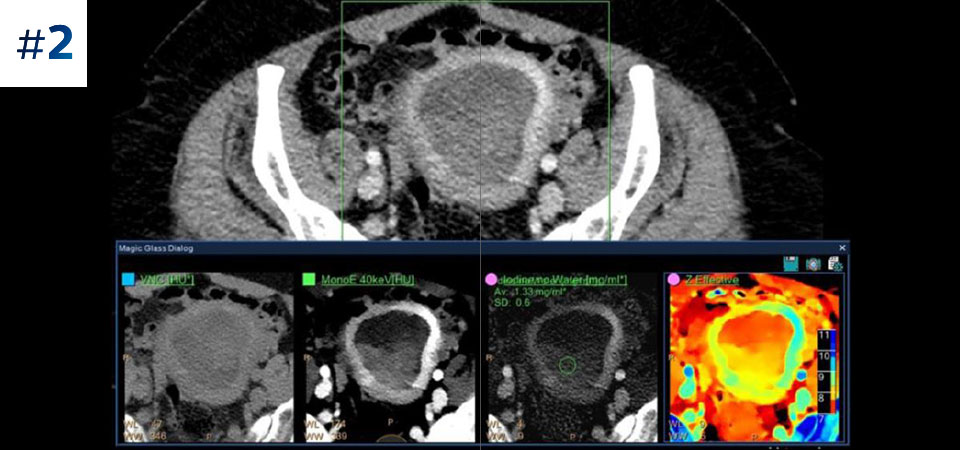

With detector-based spectral, you acquire multiple layers of data—conventional and spectral—within a single exposure and without special scan modes for improved tissue characterization and visualization.

Scan as usual A single scan for fast, low-dose conventional and spectral data for every patient, every time.

Always available 100% spectral, 100% of the time for results that are always available on-demand, even retrospectively.

Across patient types Benefits a wide range of patient types from pediatric to bariatric.